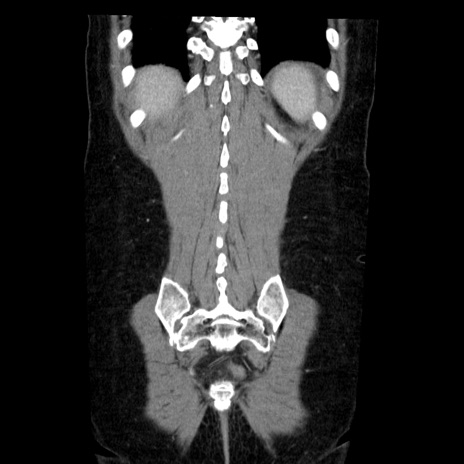

症例6(冠状断像)

【症例】50歳代女性

【主訴】下腹部痛

【現病歴】本日朝より下痢2回あり。 昼食を食べた後、嘔吐3回、下腹部痛認め、症状軽快せず、当院救急搬送。

最終食事:本日昼(生ものなし)。 昨日の夜、刺身を食ぺたとのこと。周囲に同様の症状の者なし。普段、排便は毎日あるとのこと。

【既往歴】卵巣癌術後(8年前に当院で卵巣摘出)

【身体所見】 意識清明、腹部:平坦、腸蠕動音→、やや硬、下腹部自発痛・圧痛あり、反跳痛あり、筋性防御なし。

【データ】WBC 16000、CRP 0.01